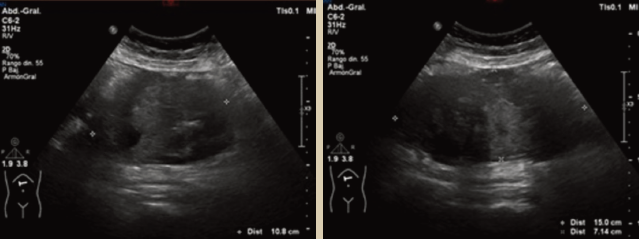

Se encontró leucocitosis, por lo que se pensó en colecistitis aguda, solicitando ultrasonido, en el que se observó lesión heterogénea de predominio hipoecoico, con zonas anecoicas difusas en su interior, ovoidea, de bordes lobulados, localizada en epigastrio con extensión hacia flanco derecho, con dimensiones en sus ejes mayores de 10.8 × 15 × 7 cm. En Doppler color se observó aumento de la vascularidad periférica, de origen por determinar, sin descartar etiología neoplásica (figuras 1a, 1b y 2).

Imagen: Argüello Ramírez et al.

Figura 1ay 1b Ultrasonido en modo B donde se observa lesión heterogénea, predominantemente hipoecoica, con zonas anecoicas difusas en su interior, ovoidea y de bordes lobulados.